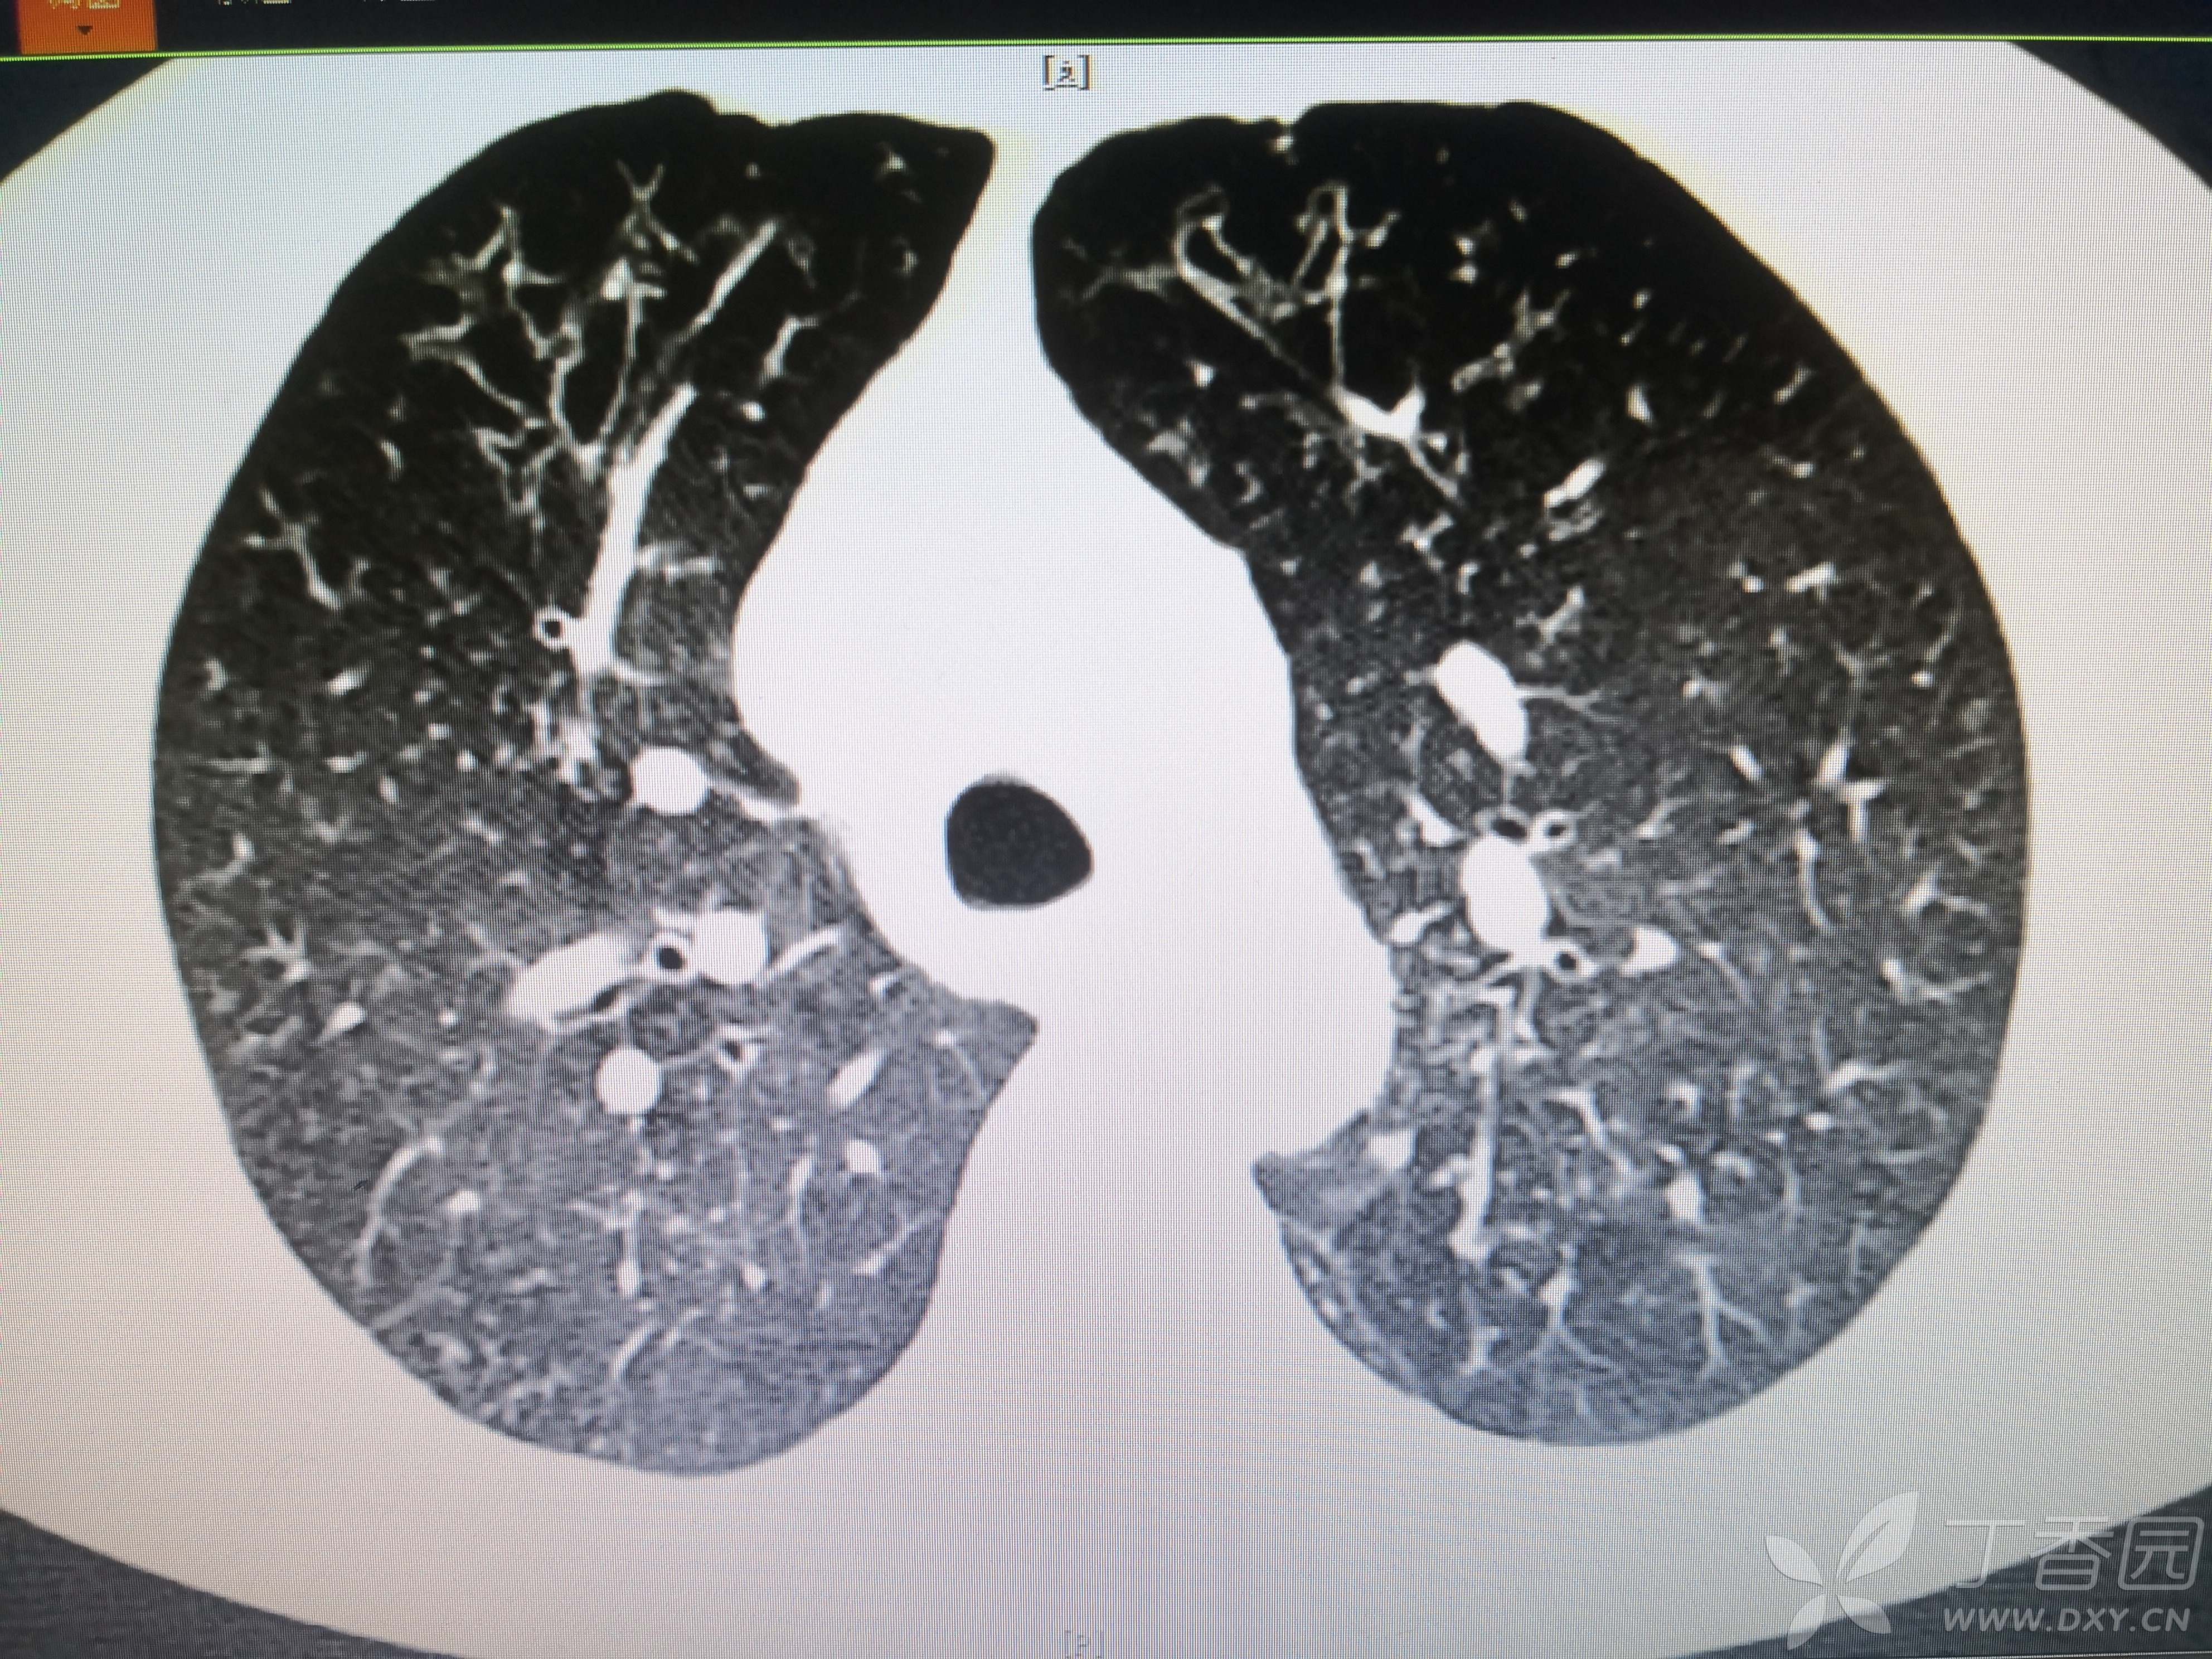

患者性别:女

患者年龄:54岁

简要病史:反复咳嗽、咳脓痰40余年,气喘10年,加剧2周。

体格检查:SpO2:72%,双中下肺闻及中小湿啰音。

辅助检查:见图

临床诊断:支气管扩张并感染

治疗经过:哌拉西林他坐巴坦联合左氧氟沙星抗感染